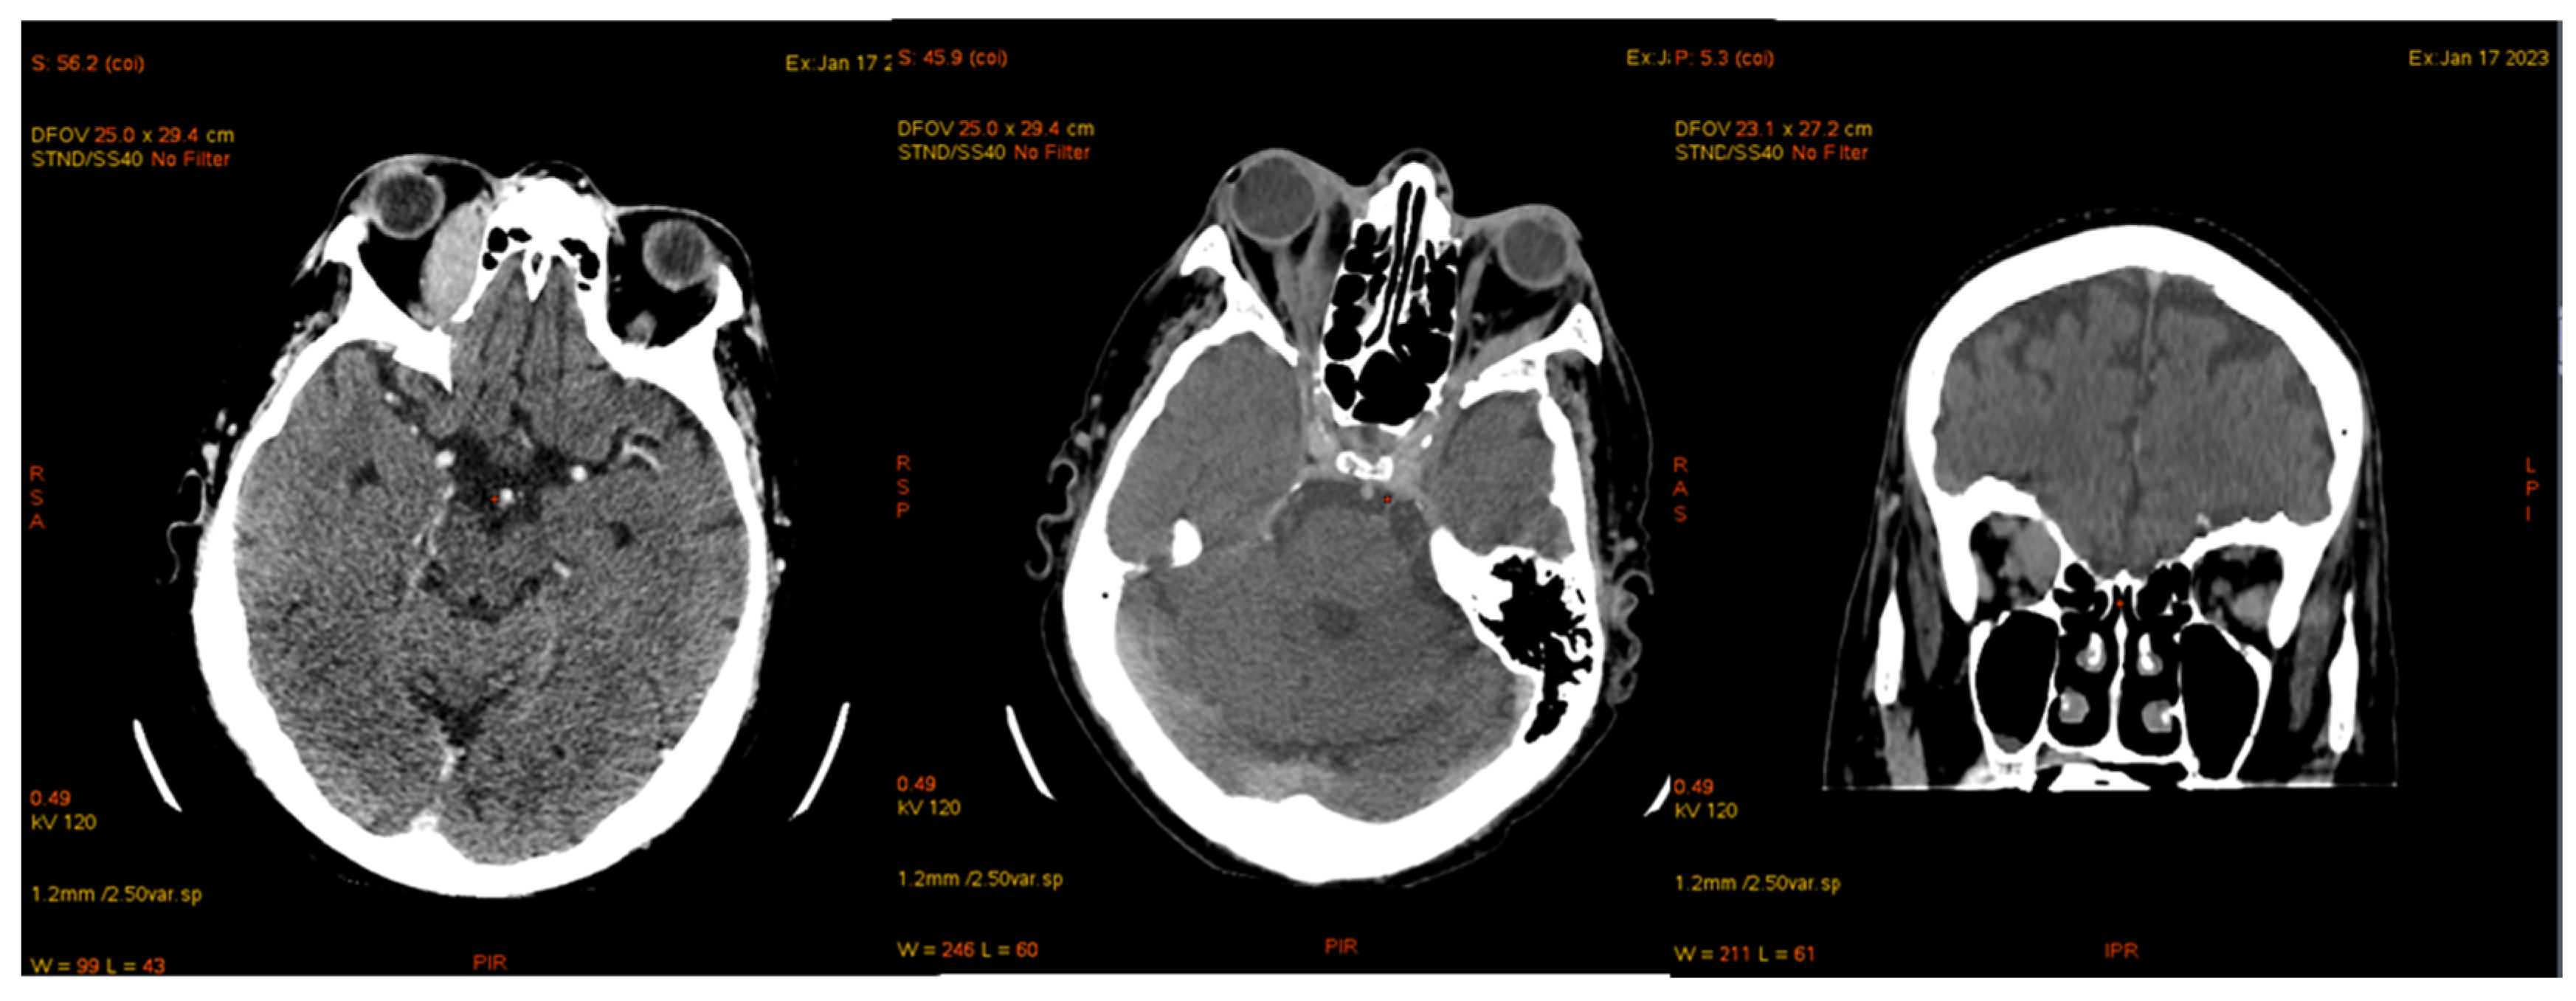

| January 2023 | second extramedullary relapse bilateral ocular left eye clinically, imaging, and biopsy demonstrated right eye demonstrated by imaging | methotrexate, asparaginase, calcium folinate radiotherapy, 30 gy/15 sessions result: imaging complete remission |